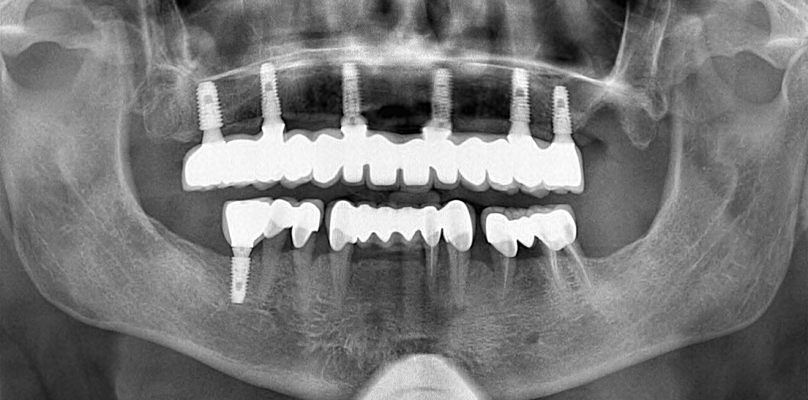

La première étape du processus de traitement consiste à prendre des images radiographiques détaillées. Ces images aident à déterminer le plan de traitement le plus approprié en évaluant la structure de votre mâchoire et votre santé dentaire. Nos radiographies révèlent à quel point le processus de traitement est extrêmement minutieux.

Dans les étapes ultérieures, vous pouvez regarder des vidéos sur la façon de placer des implants et de produire des prothèses. Ces vidéos visent à fournir une perspective informative à nos patients en montrant chaque étape du processus. Chaque étape est réalisée minutieusement par nos médecins experts.